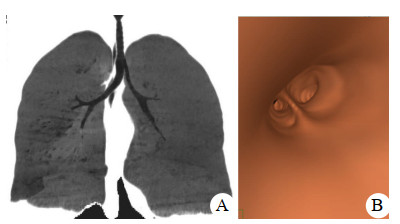

初步诊断后立即持续生命体征监测,开放静脉通路,吸氧,鼻腔填塞止血,完善实验室检查;鼻导管吸氧10 L/min,10 min后血氧饱和度仍维持在80%~85%,即准备行气管插管后再送放射科行颅脑及胸部影像学检查。急诊科医师在视频喉镜辅助下进行气管插管术(气管导管内径7.0 mm),但连续3次在确认气管导管前端进入声门5 cm后再无法置入,改用气管导管旋转或加入管芯等多种手法仍然无法置入,最后请麻醉科医师会诊。麻醉医师携带纤维支气管镜增援,当纤维支气管镜通过气管导管观察发现,远端气道狭窄。更换小号气管导管(内径5.0 mm),通过声门5 cm后仍然无法置入到位。与家属沟通,家属反馈,患者既往无呼吸系统疾病,偶有上呼吸道感染,但病程及预后无异常。患者5年前在上海一所整形医院麻醉时曾出现过这种情况,手术被院方拒绝。请耳鼻喉科、呼吸科医师会诊,建议先行颅脑及胸部影像学检查后再决定气道管理方案。CT三维重塑及虚拟支气管镜成像系统(Osirix MD version 12.0, Pixmeo SARL company)显示(图 1),气管长度仅5 cm,左右支气管内径分别为8 mm、5 mm。考虑患者手术要求及颅脑康复预后的时间,根据耳鼻喉科建议采用了气管切开导管管理气道。出院后一年随访,患者神经功能恢复良好,气管造瘘口自然愈合,发音正常,无呼吸系统并发症。

图 1 患者影像学检查结果(A:患者气管支气管CT三维重塑;B:虚拟支气管镜成像)

本例患者年轻女性,气管支气管发育先天异常。在不清楚患者气管解剖异常下气管插管,由于右侧支气管开口的位置优势,每次气管导管会顺势进入狭窄的右侧支气管并且卡塞,亦使支气管镜观察到的远端气道狭窄位置被误认为在气管。气管导管较长的套囊设计使导管需要置入至声门下6~9 cm,限制了它在气管较短患者中的使用。急诊患者多数缺乏气道影像学资料,当遇到气管导管放置困难情况时,采用纤维支气管镜对气道进行全面检查是非常必要,并且在条件允许情况下可实施纤维支气管镜引导下气管插管术。